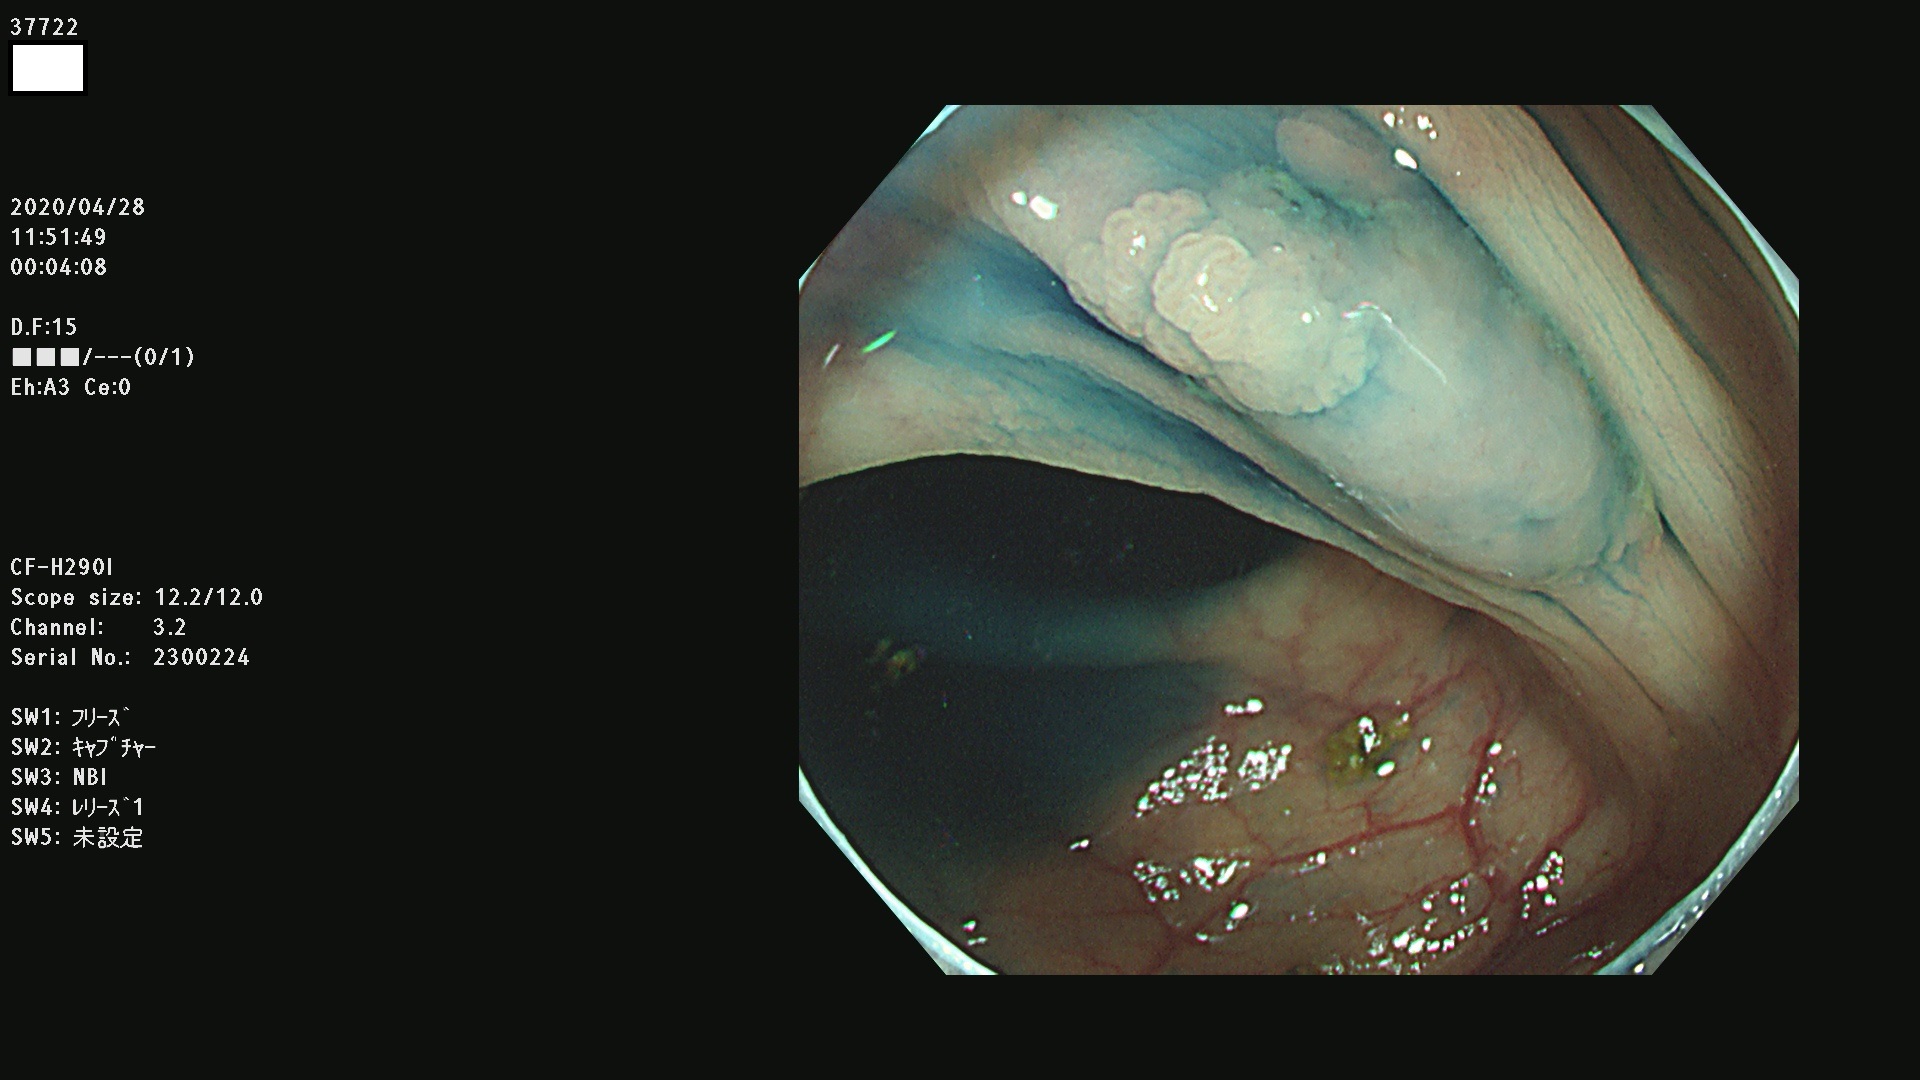

37700 37701 37702 37703 37704 37705 37706 37707(SSAPのみ) 37709 37711 37712 37715 37716 37717 37720 37722(SSAPのみ) 37724 37725 37726 37727 37728 37729 37731 37732 37733 37736(SSAPのみ) 37737 37739 37740 37741 37742 37744 37745 37748 37749 37750 37751 37752(SSAPのみ) 37753 37754 37755 37757 37758 37760 37761 37762(SSAPのみ) 37763 37764 37765 37766 37767 37768 37769 37771 37772 37774 37775 37776 37777 37780 37781 37782 37783 37784 37785 37787(SSAPのみ) 37788 37791 37792 37793 37794 37795 37799

発見困難で危険性の高い平坦型病変(上記100名より抽出)